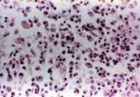

斑點熱是一組具有自然疫源性特徵的人獸共患疾病,因此,研究SFGR的生態學對研究斑 點熱是至關重要的。近40年來對SFGR的生態學研究也取得了很大的進展。現已證實SFGR是一 組經蜱或蟎叮咬傳播的專性細胞內寄生菌,野生動物參與循環,在野生動物、節肢動物與SFGR三者的生態循環中,蜱、蟎既是重要的傳播媒介又是該立克次體的保菌宿主,可經卵形成 垂直傳播,哺乳動物是節肢動物的寄主,感染蜱叮咬動物引起動物感染,健康的節肢動物叮 咬感染動物則引起蜱新的感染形成水平傳播。由此兩者之間維持著持久的SFGR感染循環。人 類只是偶然地接觸到這一個自然界的生態環節才發生感染或發病。